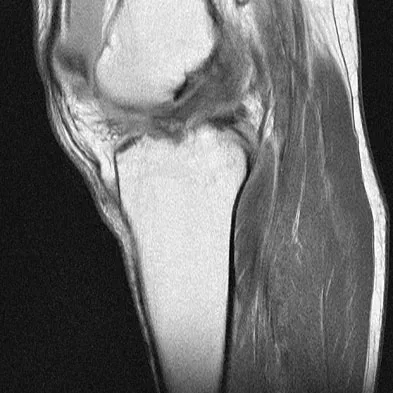

A 65-year-old man with ankylosing spondylitis has neck pain after falling back over his lawnmower, striking his thoracic spine, and forcing his neck into extension. Examination reveals subtle weakness of the intrinsics and finger flexors at approximately 4+/5. Initial management consists of immobilization in a rigid collar, and placing his head in the anatomic position. Radiographs reveal a subtle extension fracture of the lower cervical spine. Approximately 6 hours after the injury, he reports increasing paresthesias in his upper and lower extremities, and examination now shows his intrinsics are 2/5, finger flexors are 3/5, and his triceps are now weak at 4/5 on manual motor testing. In addition, his lower extremities now show weakness in both dorsal and plantar flexion of the ankle in the range of 4/5. Repeat radiographs appear unchanged. An MRI scan is shown in Figure 2. Management should now consist of

It is not uncommon for patients with ankylosing spondylitis to sustain extension-type fractures, most typically of the cervicothoracic junction. These fractures can appear nondisplaced or minimally displaced initially, making them difficult to diagnose. Because there is no mobility between vertebrae, fractures tend to occur more like those of a transverse fracture of a long bone. In addition, the vertebral bodies are vascular and their canals are relatively enclosed, making them vulnerable to epidural bleeding. The MRI scan reveals an epidural hematoma located posteriorly on the cord; therefore, the treatment of choice is surgical evacuation and a posterior laminectomy. Because of the intrinsic instability of such fractures at the time of the laminectomy, internal fixation and stabilization with a posterior fusion is warranted. A simple laminectomy will only increase instability, and control is unlikely with halo vest immobilization. An anterior procedure will not effectively treat the problem given the location of the hematoma. Consideration can be given to methylprednisolone and observation; however, this will not eradicate the problem. Bohlman HH: Acute fractures and dislocations of the cervical spine. J Bone Joint Surg Am 1979;61:1119-1142.